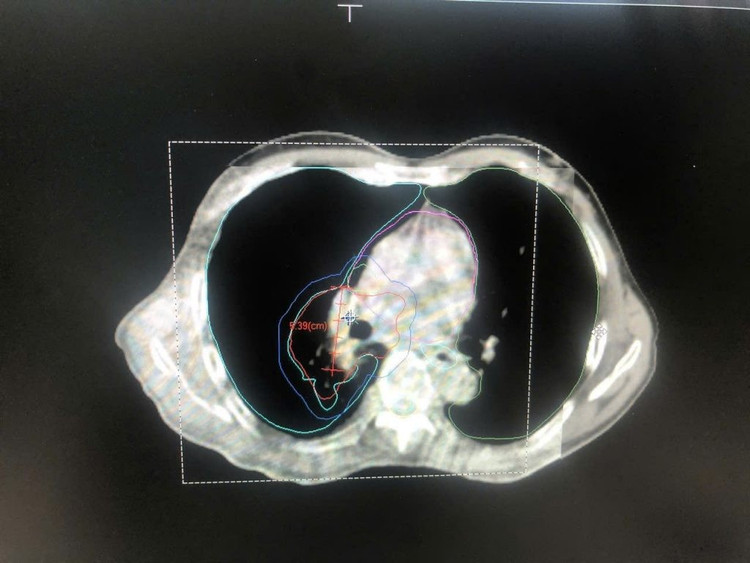

Hình ảnh CT mô phỏng cho bệnh nhân ung thư phổi để lập kế hoạch điều trị. Ảnh BV

Hình ảnh cận lâm sàng cho thấy khối ung teo nhỏ sau 5 buổi điều trị. Ảnh BV